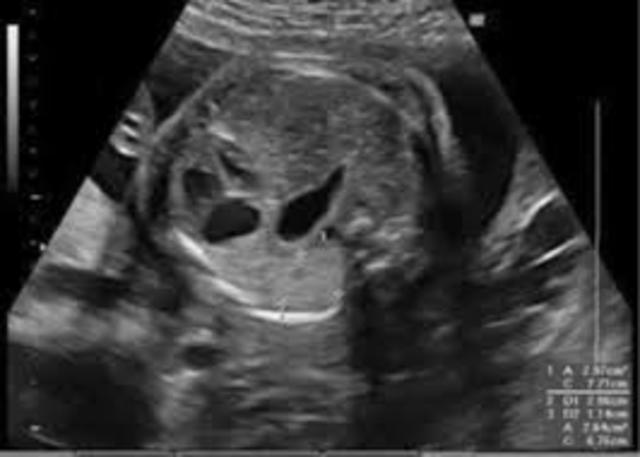

• Ecografía fetal

Ecografía fetal

"Prueba usada durante el embarazo que crea una imagen del feto en el útero materno." (Stanford Children's Health)